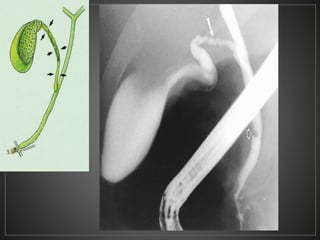

Lesión quística dilatadaque se comunica con el conducto biliar y está separada de la vesícula biliar.

• #28 CPRE conducto cístico de calibre normal (flecha sólida). contorno ondulado del conducto producido por las válvulas de Heister. Se observa una burbuja de aire (flecha abierta) en el conducto biliar común

• #39 CPRE del mismo paciente corroborando la dilatación del coledoco en forma fusiforme, corresponde a un grado Ic

• #43 CPRE se observa a nivel intramural del coledoco una acumulación de medio de contraste, en relacion a un quiste tipo III